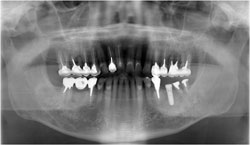

続いて、さらに1本奥の歯も腐ってしまっているので抜歯し、

歯を抜いた部分が凹むのを防ぐために人口の骨を入れました。

3ヶ月後。人口の骨が自家骨と同化するのを待ち、2本目のインプラントを埋入しました。